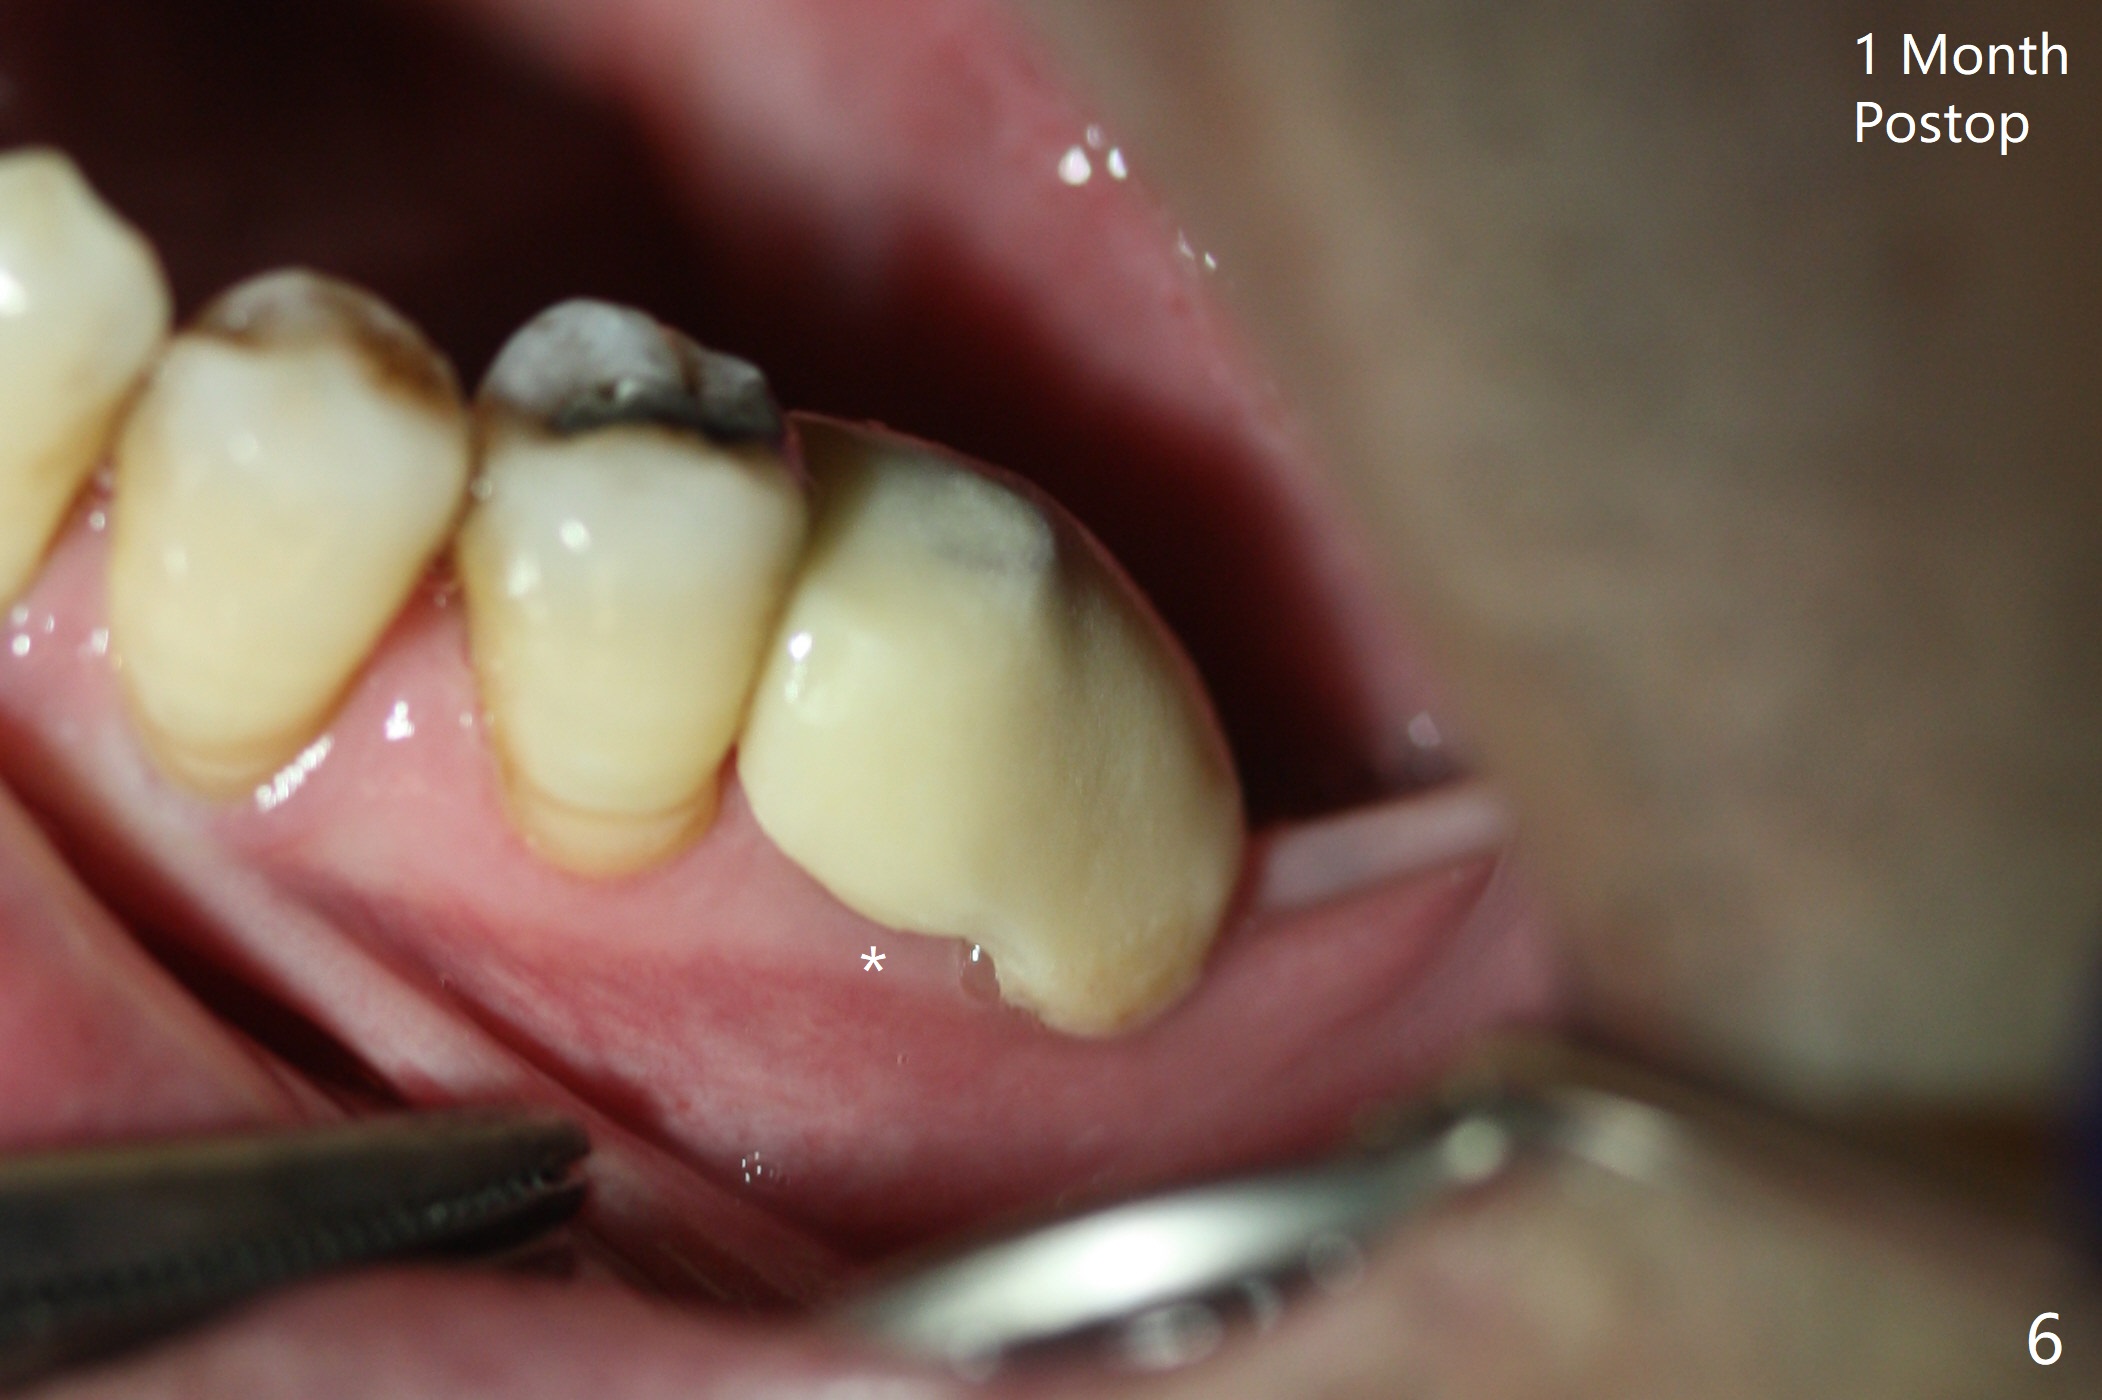

There is shrinkage in the mesial alveolus 1 month postop (Fig.6 *). When the provisional is removed 2 months postop, there is minimal amount of unincorporated bone graft (Fig.7 G) and Osteogen Plug (M, membrane). As the un-attached materials are washed up, the distal socket heals without exposure of implant threads (Fig.8 D). The bone graft settles down and remains in the distal socket 2.5 months postop (immediately pre-cementation, Fig.10 *). The bone graft appears to prevent implant threads from being exposed 2 months post cementation (Fig.11). The bone density in the distal socket increases significantly 8 months post cementation (Fig.12 *).